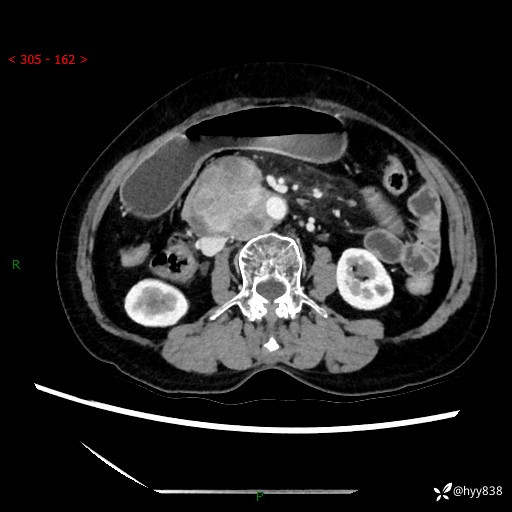

71岁/女,腹痛1月余。腹膜后肿物,间质瘤 VS 副节瘤 VS 平滑肌肉瘤---(有结果)

【患者信息】:71岁/女

【主诉】:腹痛1月余

【现病史及既往史】:患者于1月前无明显诱因出现右下腹部疼痛不适,呈阵发性隐痛,尚可耐受,放射至后背部及腰部疼痛,伴排便困难,不伴其它部位疼痛,无嗳气,无不洁饮食,无黑便,无恶心、呕吐、腹胀腹泻、呕血、发热、寒颤、厌油、黄疸,多次就诊于当地区太湖医院拍片示: 行抗炎等对症支持治疗,效果尚可。现患者上述不适症状明显进一步加重,为求进一步治疗遂来我院门诊就诊,门诊以“十二指肠肿瘤?”收住我科。 起病以来,精神、睡眠可,食欲可,大便异常、小便正常,体力、体重无明显下降。

【检查】:腹部CT增强扫描(外院CT平扫)